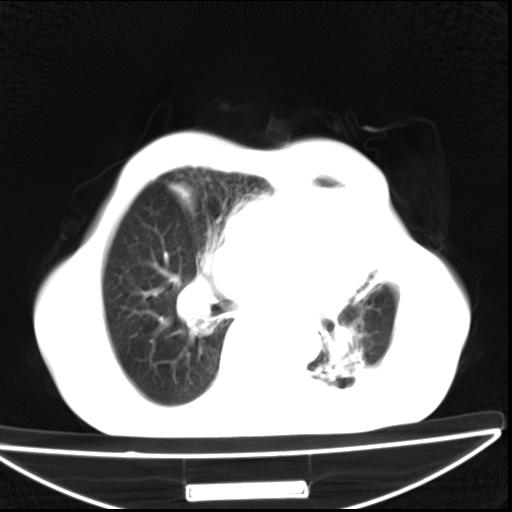

男  70岁,发烧咳嗽4天。盗汗,消瘦。无痰中带血丝,以前有肺tb病史,ct见,双肺tb,左侧胸廓塌陷,左胸膜肥厚粘连。纵隔移位,右侧胸腔积液,大家说说那个心影前左肺舌叶除了肺大炮还有炎症还是干酪性肺炎?有占位吗?我看纵隔淋巴结也大。

1)两肺继发性肺结核并左肺上叶肺不张,支气管扩张。2)双侧胸膜炎(胸膜增厚+少量胸腔积液)。

两肺继发性肺结核并感染,左肺上叶肺不张。建议ct增强。